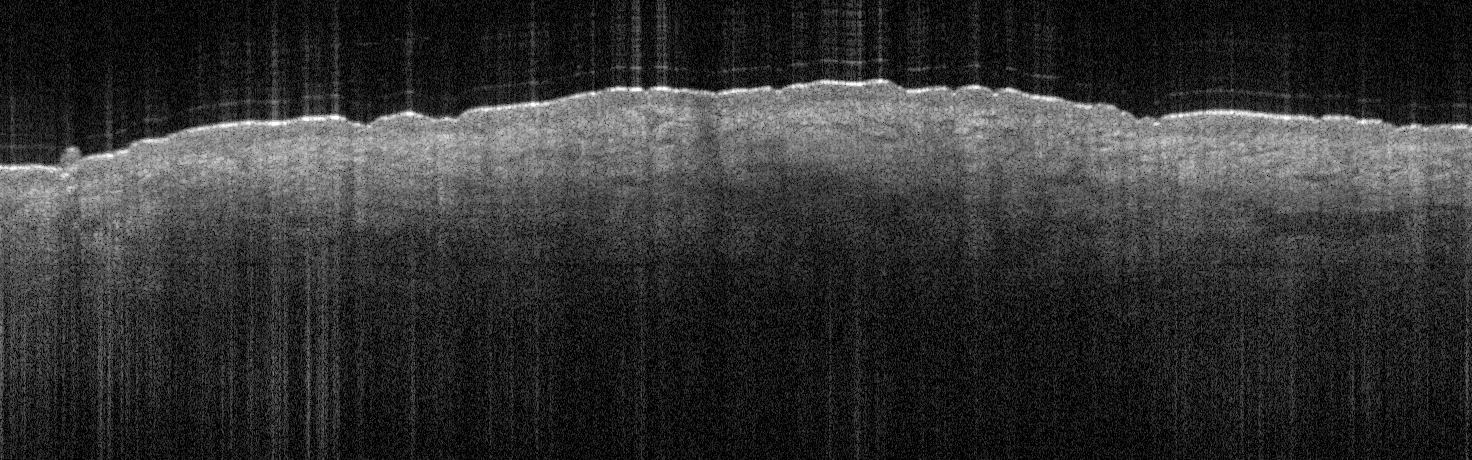

VA35: Left Temple, Actinic Keratosis, Hypertrophic

- White arrows indicate return to dermal collagen texture and reflectivity

VA35: Left Temple, Adjacent, Normal